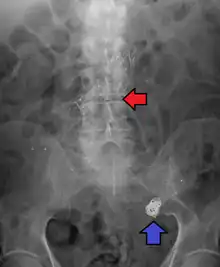

Abdominal aortic aneurysm involves a regional dilation of the aorta and is diagnosed using ultrasonography, computed tomography, or magnetic resonance imaging. A segment of the aorta that is found to be greater than 50% larger than that of a healthy individual of the same sex and age is considered aneurysmal.[9] Abdominal aneurysms are usually asymptomatic but in rare cases can cause lower back pain or lower limb ischemia.